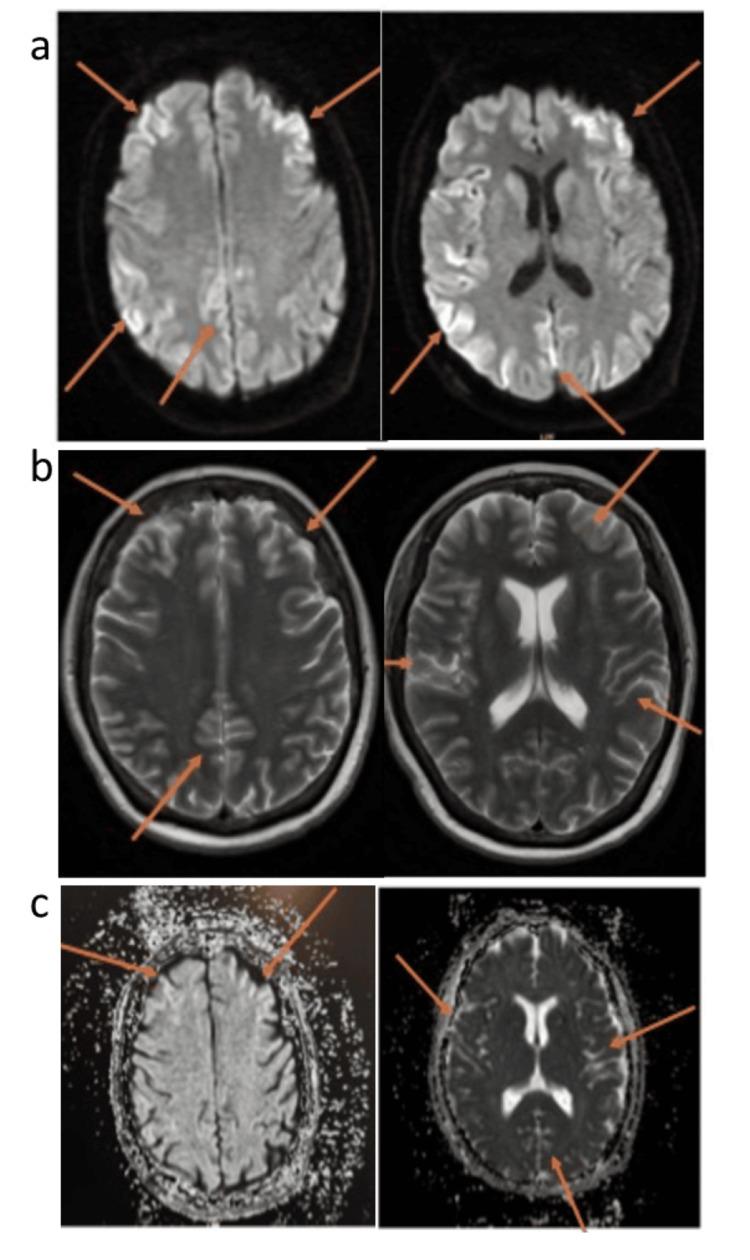

Creutzfeldt-Jakob disease (CJD) is a fatal neurodegenerative disorder that leads to rapid cognitive decline, dementia, and neurological deterioration. CJD has several forms, including sporadic CJD (sCJD), which accounts for most cases, and variant CJD (vCJD), linked to exposure to bovine spongiform encephalopathy (BSE or mad cow disease). The disease is caused by abnormal prion proteins, which damage the brain and lead to death. CJD is universally fatal, with no cure, and most cases are fatal within a few months to a year after diagnosis. We present a 64-year-old woman with a four-week history of progressive yet sudden decline in cognitive function and memory loss. There was associated decline in motor function, slumped posture, and an unsteady gait. Key findings included rapid cognitive impairment, apraxia, ataxia, hyperreflexia, and hypertonia. After extensive diagnostic examinations, including magnetic resonance imaging (MRI) head and cerebrospinal fluid real-time quaking-induced conversion (CSF RT-QuIC), she was diagnosed with sporadic Creutzfeldt-Jakob disease using criteria set by the national CJD research and surveillance unit (NCJDRSU). MRI head showed multifocal cortical ribboning on diffusion-weighted imaging and borderline right caudate hyperintensity. Unfortunately, there is no cure for CJD, and treatment is purely supportive with palliative care input, family counseling, and anticipatory medications. Her symptoms worsened quickly, and she passed away eight weeks after the onset.

克雅氏病(CJD)是一种致命的神经退行性疾病,会导致快速的认知衰退、痴呆和神经功能恶化。CJD有多种形式,包括散发性克雅氏病(sCJD),它占大多数病例,以及变异型克雅氏病(vCJD),与接触牛海绵状脑病(BSE或疯牛病)有关。该疾病由异常的朊病毒蛋白引起,这些蛋白会损害大脑并导致死亡。CJD无一例外都是致命的,无法治愈,大多数病例在诊断后的几个月到一年内死亡。我们报告一名64岁女性,有四周渐进性但突然的认知功能衰退和记忆力丧失病史。同时伴有运动功能下降、姿势萎靡和步态不稳。主要发现包括快速认知障碍、失用症、共济失调、反射亢进和张力亢进。经过广泛的诊断检查,包括头部磁共振成像(MRI)和脑脊液实时震颤诱导转化(CSF RT-QuIC),根据国家CJD研究和监测单位(NCJDRSU)制定的标准,她被诊断为散发性克雅氏病。头部MRI在弥散加权成像上显示多灶性皮质带状改变,右侧尾状核有边缘性高信号。不幸的是,CJD无法治愈,治疗完全是支持性的,包括姑息治疗、家庭咨询和预防性用药。她的症状迅速恶化,发病八周后去世。